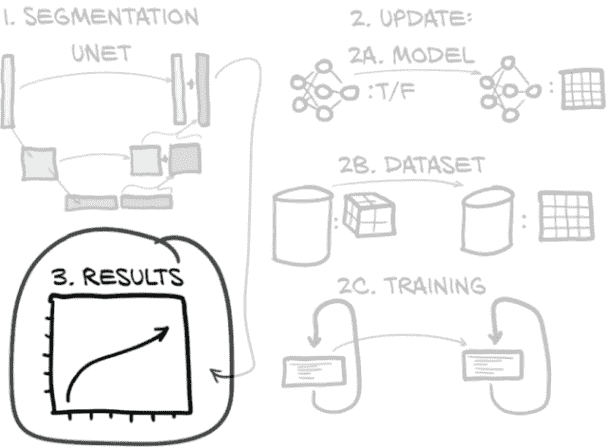

13.7 结果

现在我们已经做出了所有的代码更改,我们已经到达了图 13.17 步骤 3 的最后一部分。是时候运行 python -m p2ch13.training --epochs 20 --augmented final_seg。让我们看看我们的结果如何!

图 13.17 本章概述,重点关注我们从训练中看到的结果

如果我们限制自己只看我们有验证指标的时期,那么我们的训练指标看起来是这样的(接下来我们将查看这些指标,这样可以进行苹果对苹果的比较):

哎呀–超过 4,000% 的假正例率?是的,实际上这是预期的。我们的验证切片面积为 218 像素(512 是 29),而我们的训练裁剪只有 212。这意味着我们在一个表面是 26 = 64 倍大的切片上进行验证!假阳性计数也增加了 64 倍是有道理的。请记住,我们的真正正例率不会有实质性变化,因为它们都已经包含在我们首次训练的 64 × 64 样本中。这种情况还导致了非常低的精确度,因此 F1 分数也很低。这是我们如何构建训练和验证的自然结果,所以不必担心。

然而,问题在于我们的召回率(因此也是真正的正例率)。我们的召回率在第 5 到 10 个时期之间趋于平稳,然后开始下降。很明显,我们很快就开始过拟合,我们可以在图 13.18 中看到更多证据–虽然训练召回率继续上升,但验证召回率在 300 万个样本后开始下降。这就是我们在第五章中识别过拟合的方式,特别是图 5.14。

图 13.18 验证集召回率,在第 10 个时期后显示出过拟合的迹象(300 万个样本)

注意 请始终记住,TensorBoard 默认会平滑您的数据线。实色背后的浅色幽灵线显示了原始值。

U-Net 架构具有很大的容量,即使我们减少了滤波器和深度计数,它也能够很快地记住我们的训练集。一个好处是我们不需要训练模型很长时间!

回忆是我们对分割的首要任务,因为我们将让精度问题由下游的分类模型处理。减少这些假阳性是我们拥有这些分类模型的全部原因!这种倾斜的情况确实意味着我们很难评估我们的模型。我们可以使用更加重视召回率的 F2 分数(或 F5,或 F10…),但我们必须选择一个足够高的N来几乎完全忽略精度。我们将跳过中间步骤,只通过召回率评分我们的模型,并使用我们的人类判断来确保给定的训练运行不会对此产生病理性影响。由于我们是在 Dice 损失上进行训练,而不是直接在召回率上进行训练,所以应该会有所作用。

这是我们有点作弊的情况之一,因为我们(作者)已经为第十四章进行了训练和评估,我们知道所有这些将会发生什么。没有好的方法来看待这种情况,知道我们看到的结果会起作用。有教养的猜测是有帮助的,但它们不能替代实际运行实验直到有所突破。

就目前而言,我们的结果已经足够好,即使我们的度量有一些相当极端的值。我们离完成我们的端到端项目又近了一步!